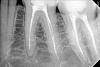

zubiki Опубликовано 4 июля, 2013 Поделиться Опубликовано 4 июля, 2013 Добрый вечер, уважаемые доктора! Я лечила 36 зуб у стоматолога, после лечения каналов зуб болел больше месяца. Я обратилась к другому стоматологу в другую клинику для консультации. Посмотрев на снимки, второй врач стала утверждать, что в канале есть фрагмент инструмента. В процессе лечения ей удалось обойти инструмент и пройти канал до верхушки. Когда я об этом рассказала первому врачу и потребовала объяснений, он сказал, что в канале ничего нет, нет сломанного инструмента. Посмотрите, пожалуйста, есть ли инструмент или его нет? Для меня это очень важно, не знаю, кому теперь доверять. Первый врач каналы сначала недопломбировал, потом еще раз переделал. Поэтому получилось 2 снимка. Второй врач говорит, что снимки свидетельствуют о низком качестве пломбировки каналов, и неудивительно, что зуб все время болит. Действительно ли пломбировка была плохая? Ссылка на комментарий

samsonov Опубликовано 4 июля, 2013 Поделиться Опубликовано 4 июля, 2013 По представленным изображениям не очень высокого качества,скорее, отломка нет,чем наоборот. Ссылка на комментарий

АнтонТЛТ Опубликовано 4 июля, 2013 Поделиться Опубликовано 4 июля, 2013 +1 на счет инструмента сложно сказать, плохое качество снимков. Пломбировка действительно так себе. Финальный снимок перелечивания есть? Ссылка на комментарий

zubiki Опубликовано 5 июля, 2013 Автор Поделиться Опубликовано 5 июля, 2013 Первые два снимка от первоисточника в цифровом формате, только последний с бумаги сканированный. Больше снимков по этому зубу пока нет, будут примерно через месяц, сейчас зуб лечится с лекарством. Но мне хотелось бы сейчас узнать истину, т.к. первый врач продолжает лечение по некоторым другим зубам, и между нами теперь испортились отношения. Он крайне оскорбился, когда я сказала, что подозреваю его в том, что он сломал инструмент в канале. Вторая врач через меня предложила ему посмотреть в канал и обнаружить там инструмент, на что он отказался, сказав, что не собирается искать "мнимый инструмент". В свою очередь первый врач предложил опубликовать мои снимки на форумах и спросить у других врачей, есть ли на снимках сломанный инструмент. Я себя чувствую крайне неловко. Между мной и первым врачом теперь царит атмосфера недоверия, в которой долечивать зубы крайне дискомфортно. Я же чувствую обиду на врача за то, что скрыл от меня, что сломал инструмент (если это так), и оставил канал непройденным (это однозначно, проходили мы его вместе со вторым врачом), успокаивая меня тем, что зуб со временем перестанет болеть сам. Я чувствую себя обманутой. Обидно просто до слез, если это так, потому что я ему доверяла, как себе. Лечила 2 года у него зубы, весь рот перелечила, он лечил всю мою семью, со временем стал чуть ли не членом нашей семьи. После этого случая я ему доверять больше не могу, подозревая в непорядочности. А для меня порядочность врача стоит наравне с профессионализмом. По какой причине канал он не прошел, если там не было инструмента? Почему он в одном корне запломбировал каналы не до верхушек в первый раз? Почему со второй попытки получилось не намного лучше? Подгружаю еще один снимок (не совсем удачный), сделанный после первого пломбирования (цифровой), если он чем то может помочь. Помогите разрешить спор - есть ли инструмент, или его нет. Вторая врач настолько же уверена в том, что инструмент там есть, насколько первый уверен в том, что его там нет. Первый предлагает сделать томографию для проверки, вторая врач с большим старанием пыталась вымыть инструмент из канала, будучи полностью уверенной, что он там есть. Вопрос для всех троих принципиальный. Ссылка на комментарий

Magdalena Опубликовано 6 июля, 2013 Поделиться Опубликовано 6 июля, 2013 (изменено) Сломанного инструмента не вижу. Если инструмент сломан и обойден рядом и канал запломбирован на всю длину - прогноз хороший, сам по себе отломок опасности не представляет.Если зуб у Вас в состоянии как в посте №2, т.е. с недочищенным по стенкам материалом, то отличить оставшийся материал от отломка по КТ проблематично. Изменено 6 июля, 2013 пользователем Magdalena 1 Ссылка на комментарий